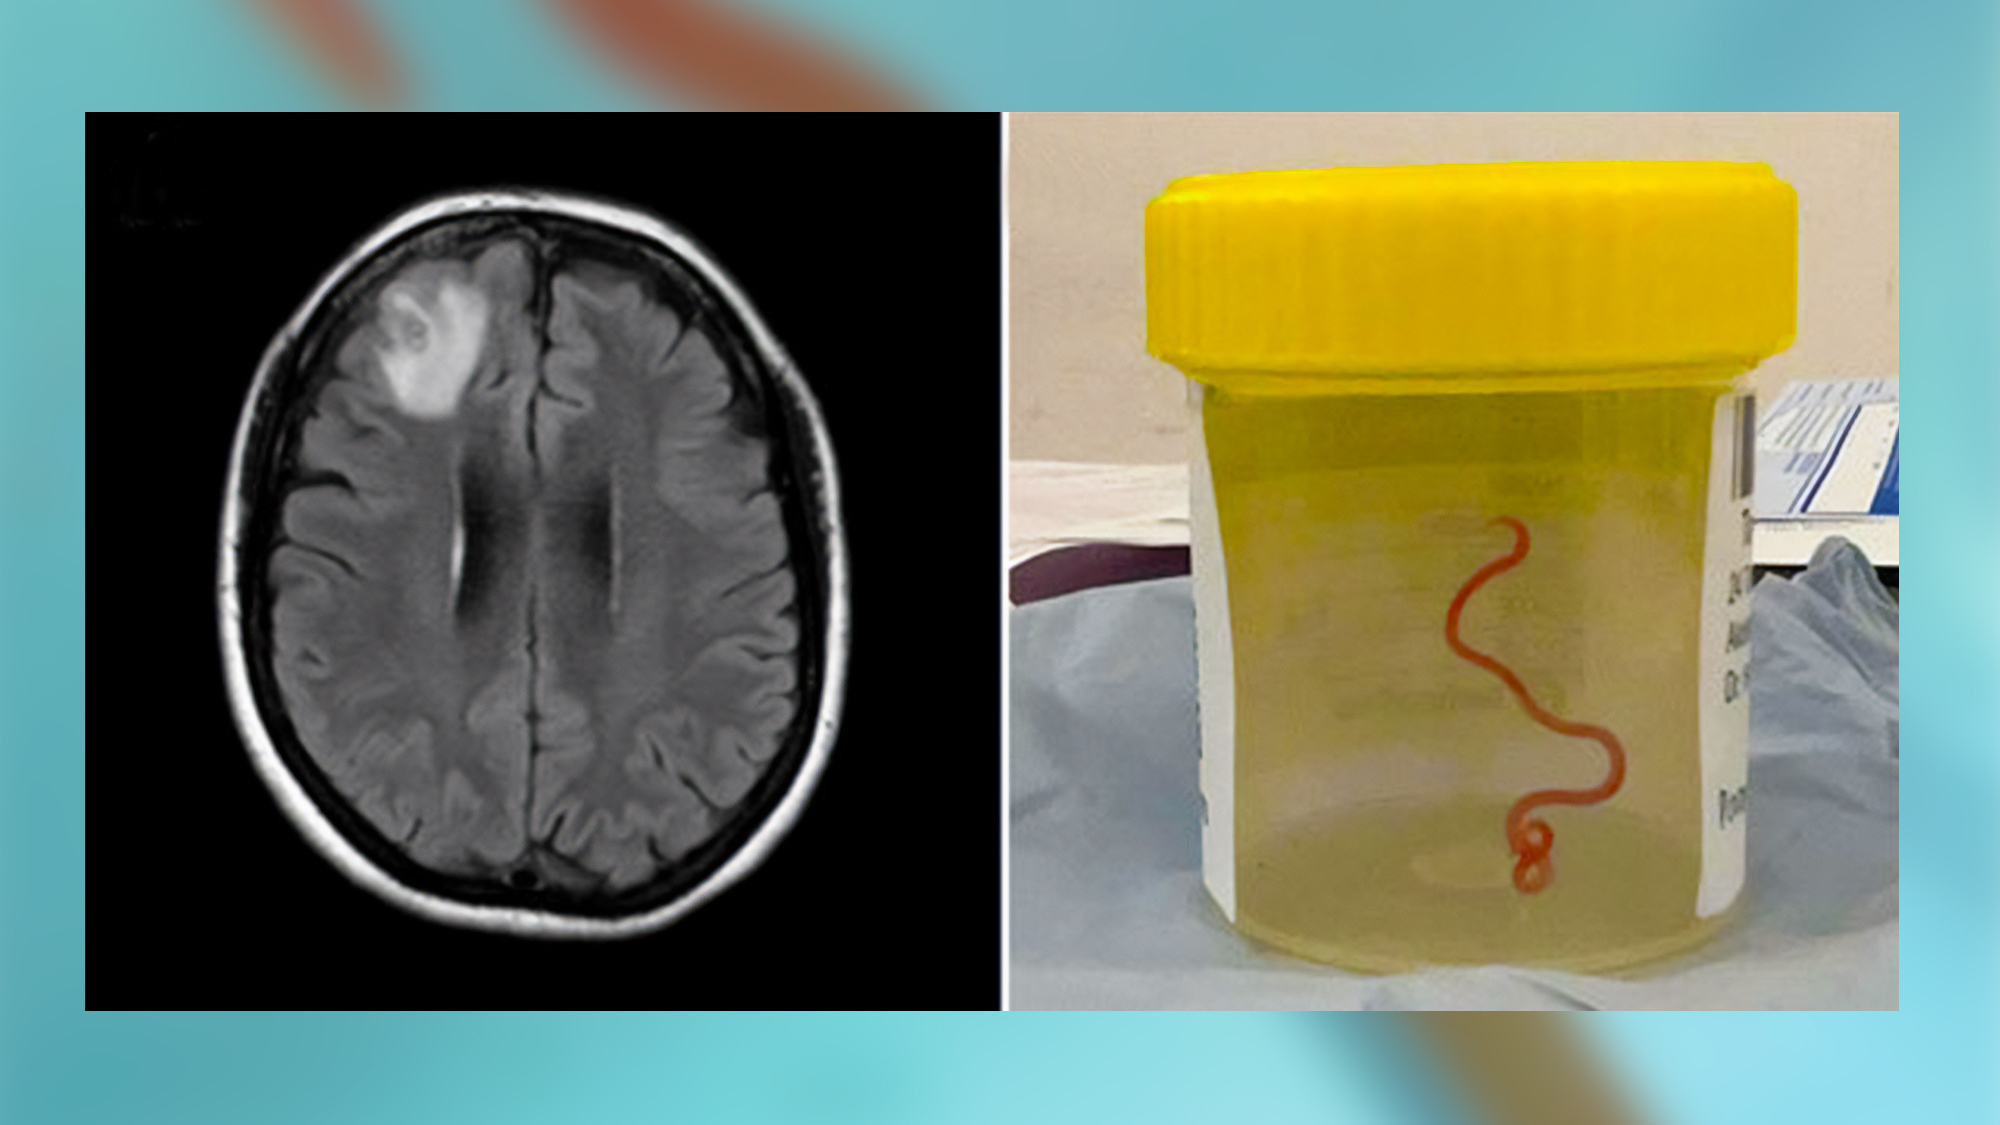

A live third-stage larval form of Ophidascaris robertsi that is about 3 inches long and only one millimeter in diameter. The worm is seen under a stereomicroscope.

A live third-stage larval form of Ophidascaris robertsi that is about 3 inches long and only one millimeter in diameter. The worm is seen under a stereomicroscope. CREDIT: Hossain M/Kennedy KJ/Wilson HL.